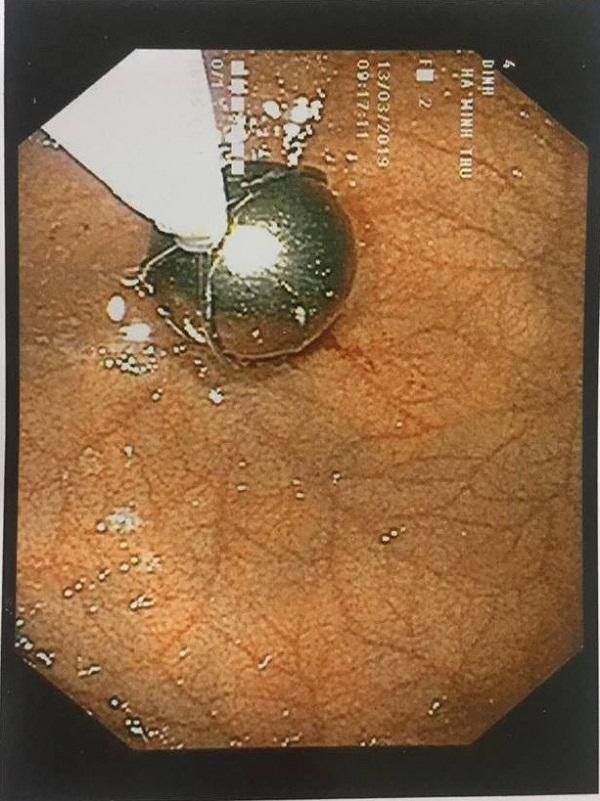

Bác sĩ Hội cũng cho biết thêm, nội soi gắp dị vật cho trẻ nhỏ nói chung và ở trường hợp bé T. rất phức tạp, các sự cố y khoa xảy ra khi nội soi tai mũi họng đa phần là do tâm lý trẻ lo sợ, không hợp tác, cựa quậy khi nội soi.

Hình dạng dị vật tròn và rất trơn tuột, gắp ra rất khó khăn, bác sĩ đã phải dùng rọ gắp sỏi chuyên biệt và tập trung tinh thần cao độ, thận trọng hết sức. Nếu sơ sấy để viên bi rơi vào khí quản thì chỉ sau 3 phút trẻ có thể bị di chứng não suốt đời và trong vòng 5 phút trẻ có nguy cơ bị tử vong.